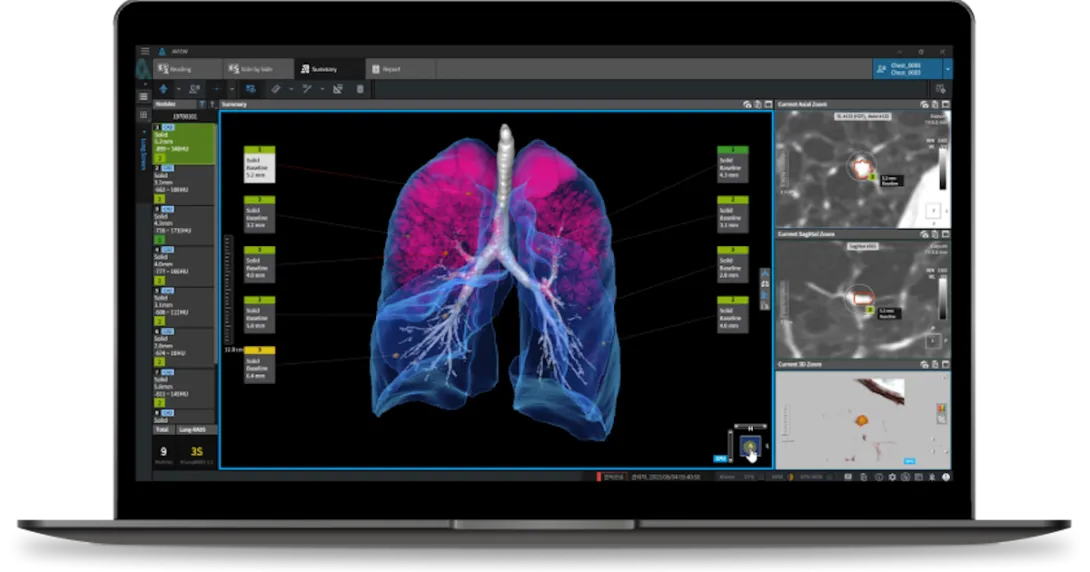

Another Korean company, Coreline Soft, bagged contracts in Europe to supply its AI screening software.

Following a competitive bidding process, it will provide the University Hospital Lausanne in Switzerland with its flagship product, AVIEW LCS Plus, which uses AI to identify lung nodules, pulmonary emphysema, and coronary artery calcification in chest X-rays.

The same software is also being implemented in the respective lung disease research of two French hospitals, the Bichat–Claude Bernard Hospital under Europe's largest hospital system, Assistance Publique–Hôpitaux de Paris, and the private, not-for-profit Foch Hospital in Suresnes, a commune in western Paris.

Hospital del Mar, a general hospital in Barcelona, Spain, is also adopting Coreline's AI screening tool for its clinical research on lung cancer. The hospital is part of the European lung cancer screening project, 4-In-The-Lung-Run, of which Coreline is also a technology partner.